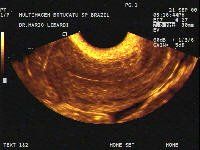

Three-dimensional ultrasound (3D US) is a new imaging modality, which is being introduced into clinical practice. Although this technique will not probably replace two-dimensional ultrasound, it is being increasingly used.